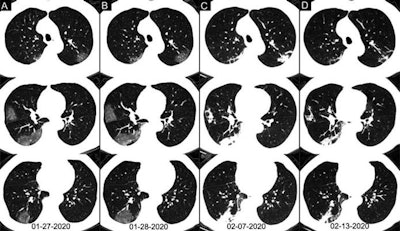

Axial chest CT images of a 62-year-old man with COVID-19 showing disease progression over time, from bilateral ground-glass opacities on 27 January (A) to multifocal organizing consolidation on 13 February (D). He had multiple negative results from RT-PCR tests, including those obtained on 3 and 11 February. Image courtesy of the RSNA.Overall, the researchers found that chest CT was better at diagnosing COVID-19 than RT-PCR testing upon initial examination of high-risk individuals. The initial RT-PCR testing period included multiple repeat tests up to three days after presentation.

Initial RT-PCR testing detected COVID-19 in only 59% of the cases. In comparison, 88% of the patients showed chest CT findings indicative of COVID-19. Among those with negative initial RT-PCR results, 93% showed CT features consistent with COVID-19 diagnosis prior to eventual confirmation on RT-PCR four or more days after the initial test.